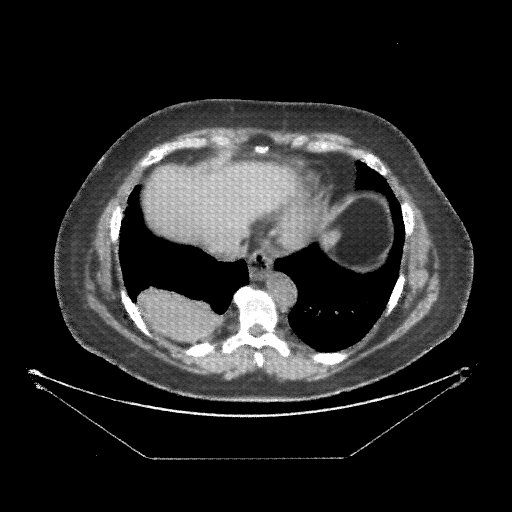

Generated VENOUS CT scan (A→B translation)

Full window (WL 1023.5, WW 4095 β†’ Low βˆ’1024, High +3071)

Lung window (WL -600, WW 1500 β†’ Low βˆ’1350, High +150)

Mediastinum window (WL 40, WW 400 β†’ Low βˆ’160, High +240)